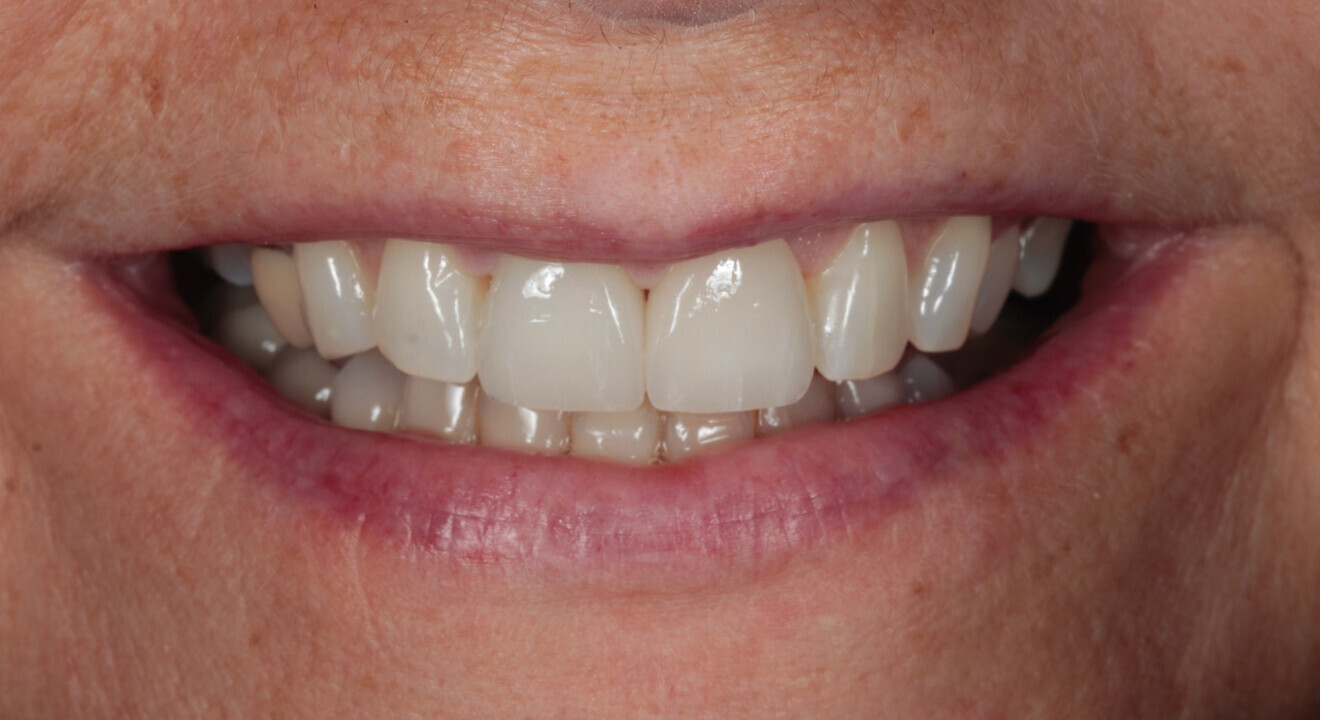

In 2021, the patient decided to have the two maxillary central incisor restorations replaced with a lithium disilicate crown and veneer (Fig. 13). The maxillary palatal platforms created with Venus Diamond in 2017 were still functional, and the repaired mandibular central incisal edge was still intact (Figs. 14 & 15). The original edge bonding on the other mandibular teeth still remained in place, 17 years later.

This case effectively demonstrates that the concept of “pausative” dentistry can be aesthetic, functional and affordable. If this patient’s teeth had been left untreated from 2004, how would they have looked 17 years later? The mandibular crowding would likely have worsened.2 The bite would probably have deepened, causing more surface loss, as there were already signs of dentine exposure. The already reduced posterior guidance would likely have worsened and more posterior teeth may have failed.

The “pausative” approach with alignment and direct edge bonding according to the Dahl principle can help to minimise the amount of damage in long-term cases (Fig. 16). It can help prevent further tooth surface loss and tooth positional changes and hold the occlusion in a much better position over time.

Fig. 16: 2021—the patient’s teeth 17 years later thanks to interceptive treatment with alignment and direct edge bonding according to the Dahl principle to minimise the amount of damage.